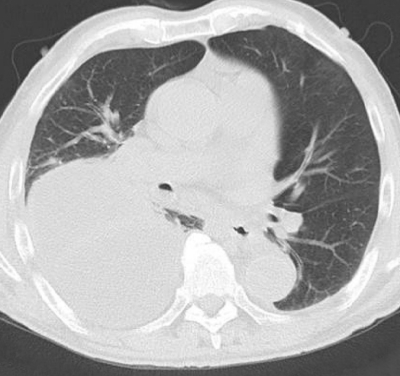

検査所見:血液所見:赤血球 355 万、Hb 12.1 g/dL、Ht 36 %、白血球 16,500 (桿状核好中球 25 %、分葉核好中球 65 %、好酸球 1%、単球 2%、リンパ球 7%)、血小板 40 万。血液生化学所見:総蛋白 5.9 g/dL、アルブミン 2.2 g/dL、AST 29 U/L、ALT 18 U/L、LD 173 U/L(基準 176〜353)、ALP 223 U/L(基準 115〜359)、γ-GTP 44 U/L(基準 8〜50)、CK 260 U/L(基準 30〜140)、尿素窒素 35 mg/dL、クレアチニン 1.6 mg/dL、血糖 161 mg/dL、HbA1c 5.7 % (基準 4.6〜6.2)、Na 131 mEq/L、K 4.3 mEq/L、Cl 97 mEq/L、Ca 8.4 mg/dL。CRP 31 mg/dL。動脈血ガス分析(room air):pH 7.55、PaCO2 32 Torr、PaO2 56 Torr、HCO3- 28 mEq/L。心電図で異常を認めない。臥位のポータブル胸部エックス線写真と胸部CTとを別に示す。

この画像所見をきたす原因として最も考えられるのはどれか。